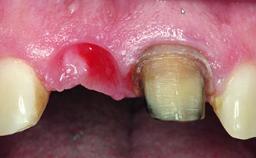

Replacement of a Compromised Upper Right Central Incisor: Hard- and Soft-tissue Augmentation, Late Placement of an RC Bone Level Implant

A 36-year-old male patient with a compromised maxillary central incisor was referred by his general dentist for consultation. The patient’s chief complaints were the gradual debonding of a temporary crown on the right central incisor and unsatisfactory esthetics due to an increasing diastema between the right central and lateral incisors. The patient reported a traumatic event some years previously, when a crown had been placed after root-canal treatment. The referring dentist wanted to provide a new crown restoration, but was concerned about the condition of the residual root. Anamnesis was negative for any other dental or periodontal pathology in the remaining dentition. The patient reported taking no medications: He was a smoker (10 to 15 cigs/day) and had realistic esthetic expectations.

Soft Tissue Anatomy Intact Defective

Soft Tissue Contour and Volume Slightly compromised